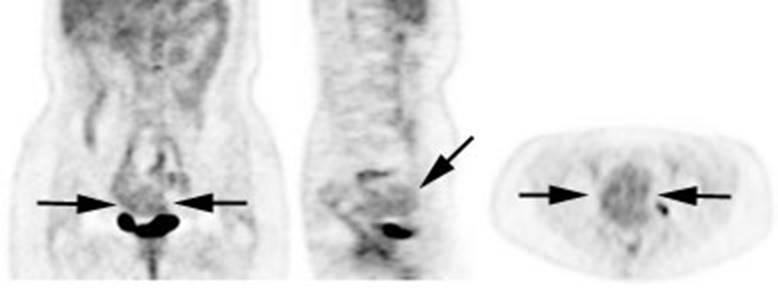

Figure 25 - Normal

testicular activity: Mild

symmetric testicular uptake can be seen (black arrows)

Figure 26 - Normal